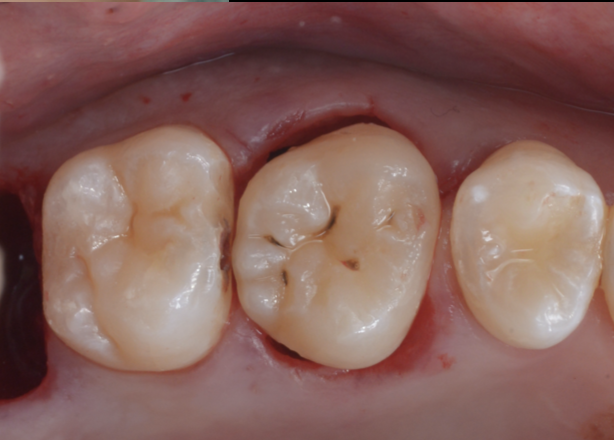

4)セラミック修復(形態・適合・清掃性を最適化)

移植歯は、形が欠損部位に完全一致するとは限りません。

そのため最終的に噛み合わせ・歯の形・清掃性を整える補綴設計が重要です。セラミック等で適合と形態を追い込むことで、歯周環境や咬合負担を改善できます。